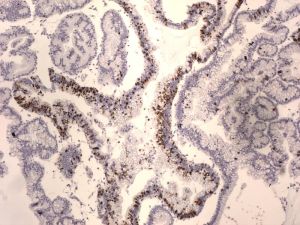

腸炎病菌第一:腸鳴表現單獨存在,其病因主要是消化不良。腸道產氣過多,且不能順暢循環。危害性較小。治療上主要以收斂藥或調理藥物為主。

第二:並存諸多症狀,且發作時間累計一月以上者。就預示腸炎、胃炎的存在。這類患者較容易出現消化不良,不能充分吸收營養,一方面造成營養的流失和必須營養的供給,勢必給正常的生理需求造成較大的危害。尤其是女士和中老年朋友,一旦出現類似病情,輕則營養不良,重則脫水,引發失眠,膚色暗黃,消瘦,慢性病急性發作或加重病情。連續3月者,較容易導致惡性循環的胃腸炎症。給治療帶來較大的影響。